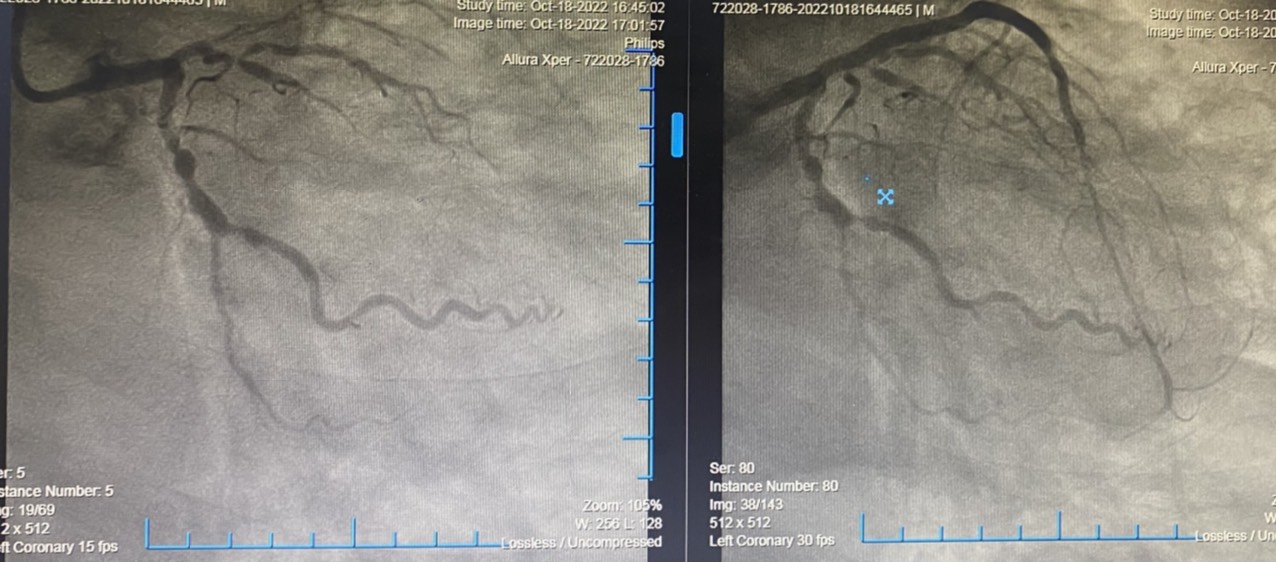

Đến ngày 17/10 vừa qua, với sự tin tưởng, bệnh nhân quyết định đến Bệnh viện đa khoa quốc tế Hải Phòng để thực hiện tiếp can thiệp mạch vành tại những vị trí tắc hẹp còn lại. Qua kết quả chụp mạch vành cho thấy hình ảnh xơ vữa, vôi hóa tắc hoàn toàn mạn tính LAD I-II và có tuần hoàn bàng hệ từ vành phải và động mạch mũ sang, Stent cũ RCA II thông tốt, hẹp 90% động mạch mũ. Siêu âm tim thấy tình trạng rối loạn vận động vùng của tim phải và tim trái đã cải thiện nhiều so với lần nhồi máu cơ tim cấp hồi tháng 05/2022. Sau khi hội chẩn và đánh giá, không có vùng nào của tim trái là vô động, chủ yếu là giảm động vừa – nhiều, diện tưới máu của LAD là rất lớn, nếu tái thông tốt sẽ giúp cải thiện tình trạng suy tim của bệnh nhân hơn nữa. Ekip can thiệp đã quyết định tiến hành can thiệp tắc mạn tính động mạch vành đoạn LAD I – II. Can thiệp CTO tắc mạn tính mạch vành là thủ thuật khó, phức tạp, nguy cơ biến chứng cao, đòi hỏi bác sĩ thực hiện can thiệp phải có trình độ cao, nhiều kinh nghiệm đồng thời cần dùng nhiều dụng cụ can thiệp đặc biệt. Kíp can thiệp trực tiếp do ThS. Vũ Học Huấn – Trưởng Khoa Tim mạch Đột quỵ; ThS.BS Phạm Văn Thuận – Khoa Tim mạch, Đột quỵ cùng cộng sự đã tiến hành tái thông LAD I – II và đặt stent vị trí tắc mạn tính thành công. Sau can thiệp, ghi nhận dòng chảy tốt TIMI 3, tưới máu cơ tim được thiết lập lại.

- Hình ảnh trước và sau can thiệp của bệnh nhân